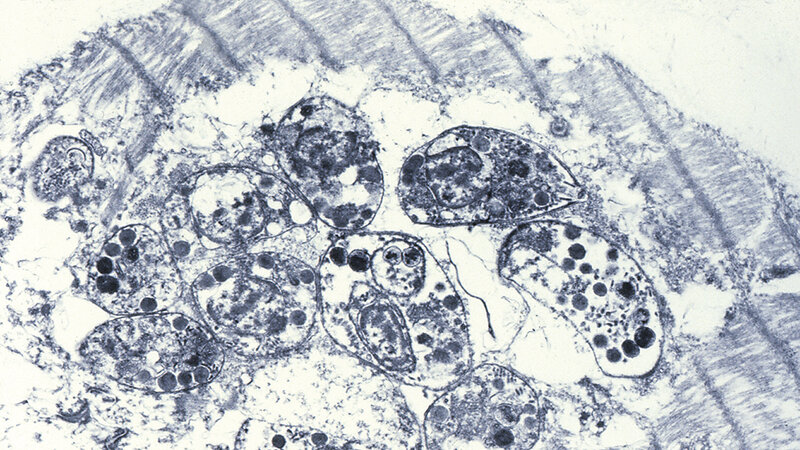

Die Toxoplasmose ist weltweit verbreitet. Sie ist eine der häufigsten Infektionskrankheiten des Menschen. Der Erreger Toxoplasma gondii gehört innerhalb der Protozoen zu den Sporozoiten. Der Mensch infiziert sich in der Regel peroral durch Aufnahme von Oozysten mit lebensfähigen Trophozoiten, durch mit Katzenkot kontaminiertes Gemüse und Obst oder durch direkten Kontakt mit Oozysten bei der Gartenarbeit. Eine Infektion ist aber auch durch den Genuss von unzureichend erhitztem zystenhaltigen Fleisch (Schwein, Schaf, Ziege) möglich. Eine Toxoplasmose verläuft in circa 90 % der Fälle inapparent mit Bildung von trophozoitenhaltigen Zysten im Gewebe, die jahrzehntelang persistieren können und somit eine Immunität aufrechterhalten. Von klinischer Relevanz sind Reaktivierungen einer latenten Infektion bei immunsupprimierten Personen sowie die erstmalige Infektion während der Schwangerschaft mit daraus sich entwickelnder pränataler Toxoplasmose. Die meisten pränatal infizierten Kinder weisen bei der Geburt keine Symptome auf, können aber bis zum 20. Lebensjahr Spätschäden entwickeln.